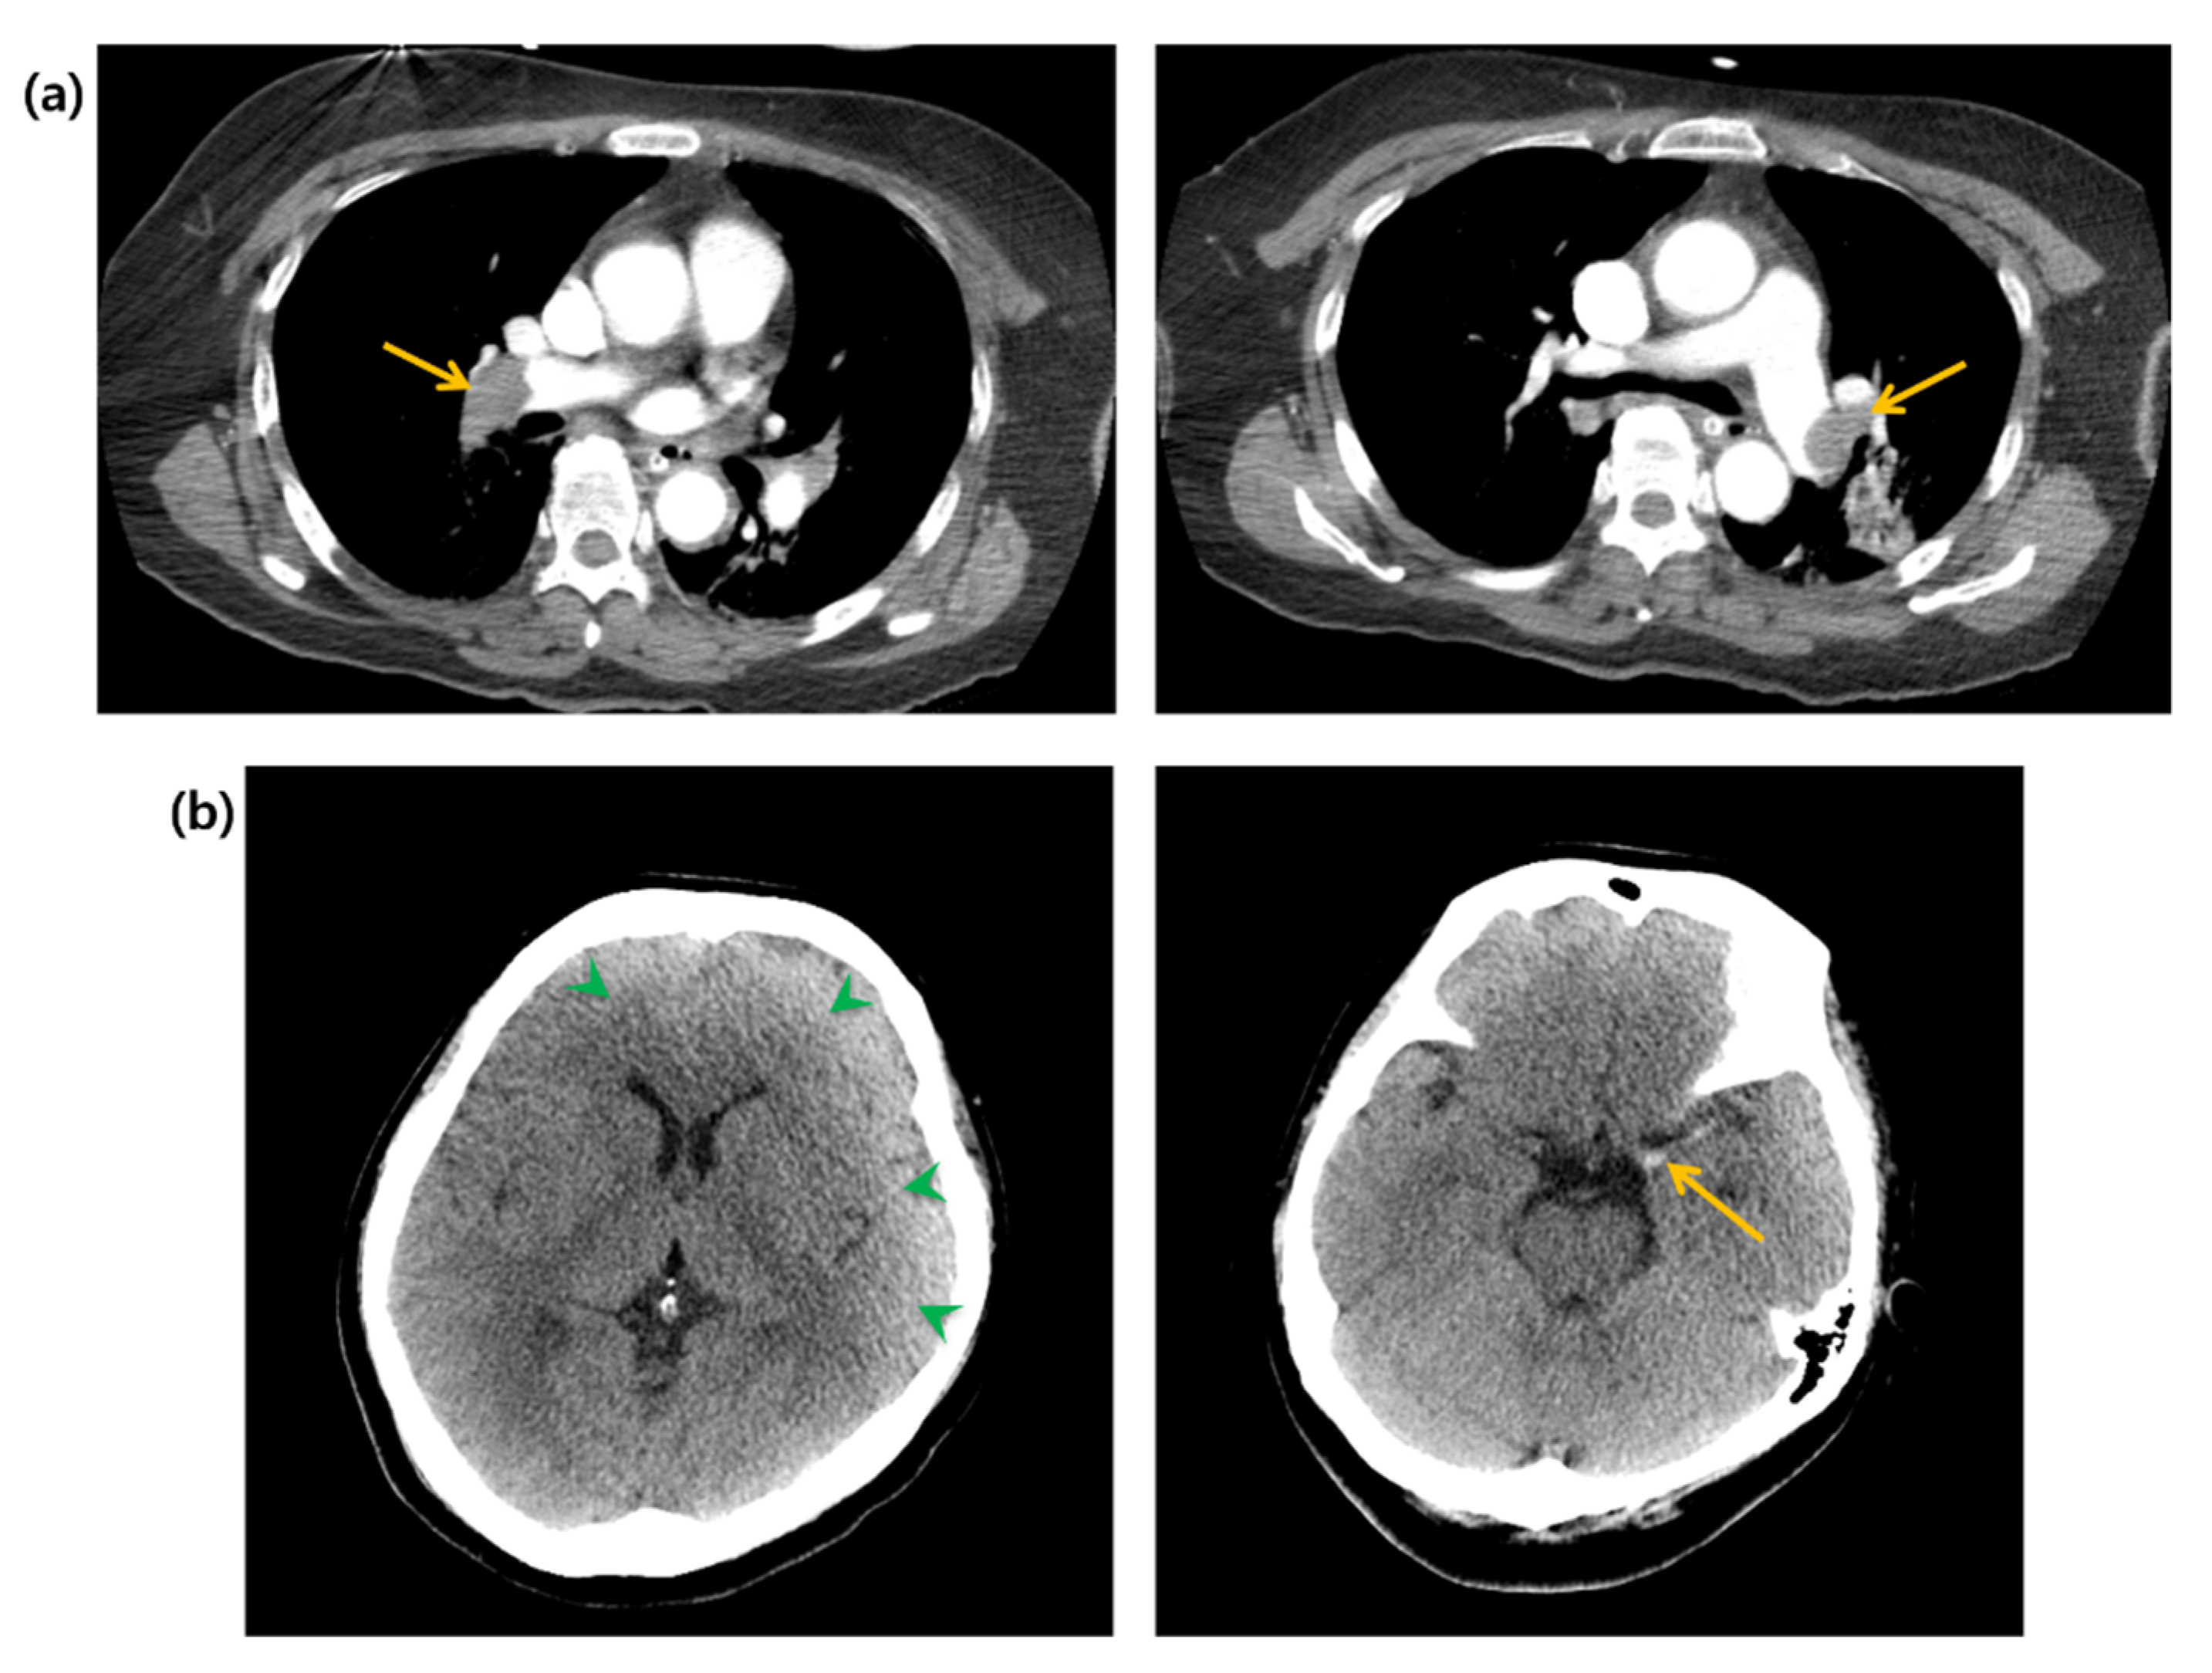

2. Case Presentation